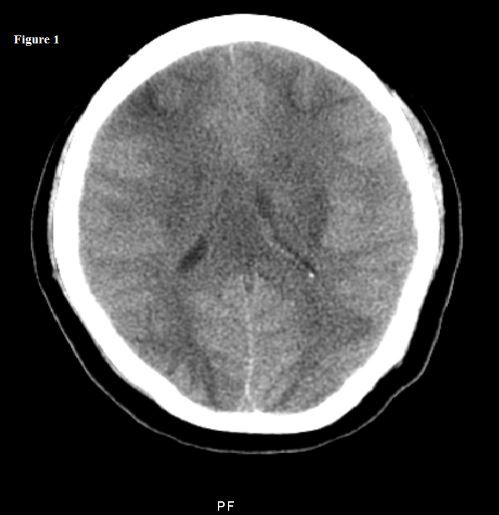

A 22-year-old pregnant woman presented at 36 weeks of gestation with a 1-day history of mild headache, blurred vision, and epigastric pain. Her blood pressure was 175/120 mm Hg. A brain CT scan without contrast showed marked diffuse vasogenic cerebral edema and partial bilateral uncal herniation and effacement of the suprasellar cistern. Bilateral low attenuation of the frontal and occipital lobes probably resulted from marked edema.